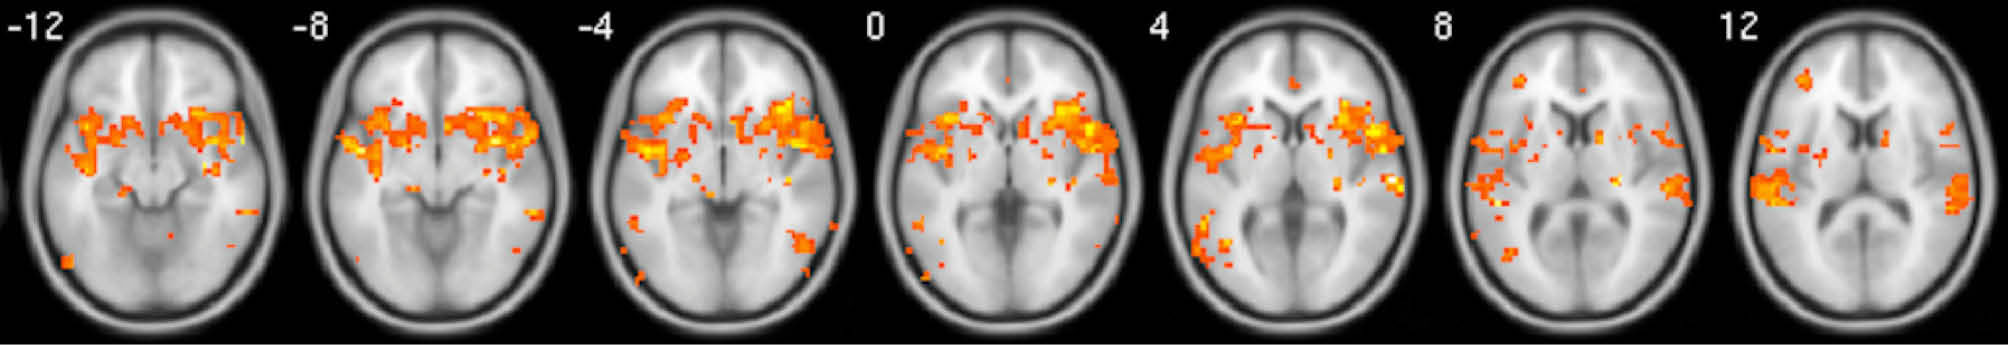

Fig. 4.

Whole brain activation during tingling moments when contrasted with baseline moments. Activations have been FDR corrected and were observed in the mPFC, as well as, a variety of regions notably surrounding the NAcc and Insula. Images are average brain activations across all subjects.

When relaxing moments were compared with baseline moments, a small but significant cluster of activation appeared in the mPFC after FDR correction, but not for the vACC (Fig. 3). Other horizontal slices showed little significant activity. When tingling moments were compared with baseline moments, multiple and significant clusters of activation appeared in the mPFC, insula, and NAcc after FDR correction (Fig. 4).